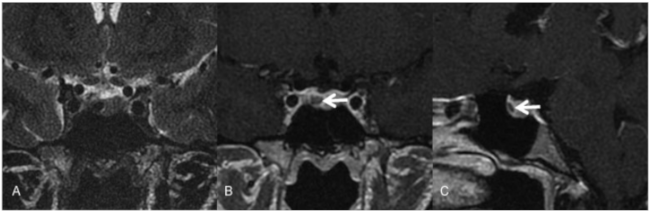

Adenoma de hipófisis en un paciente con MEN tipo 1. Imágenes de resonancia magnética (RM). En la secuencia potenciada en T2 en el plano coronal se objetivó una lesión redondeada hipointensa en la porción derecha de la adenohipófisis (flecha). Las imágenes con gadolinio en el plano coronal (B) y sagital (C) mostraron la lesión nodular no captante.